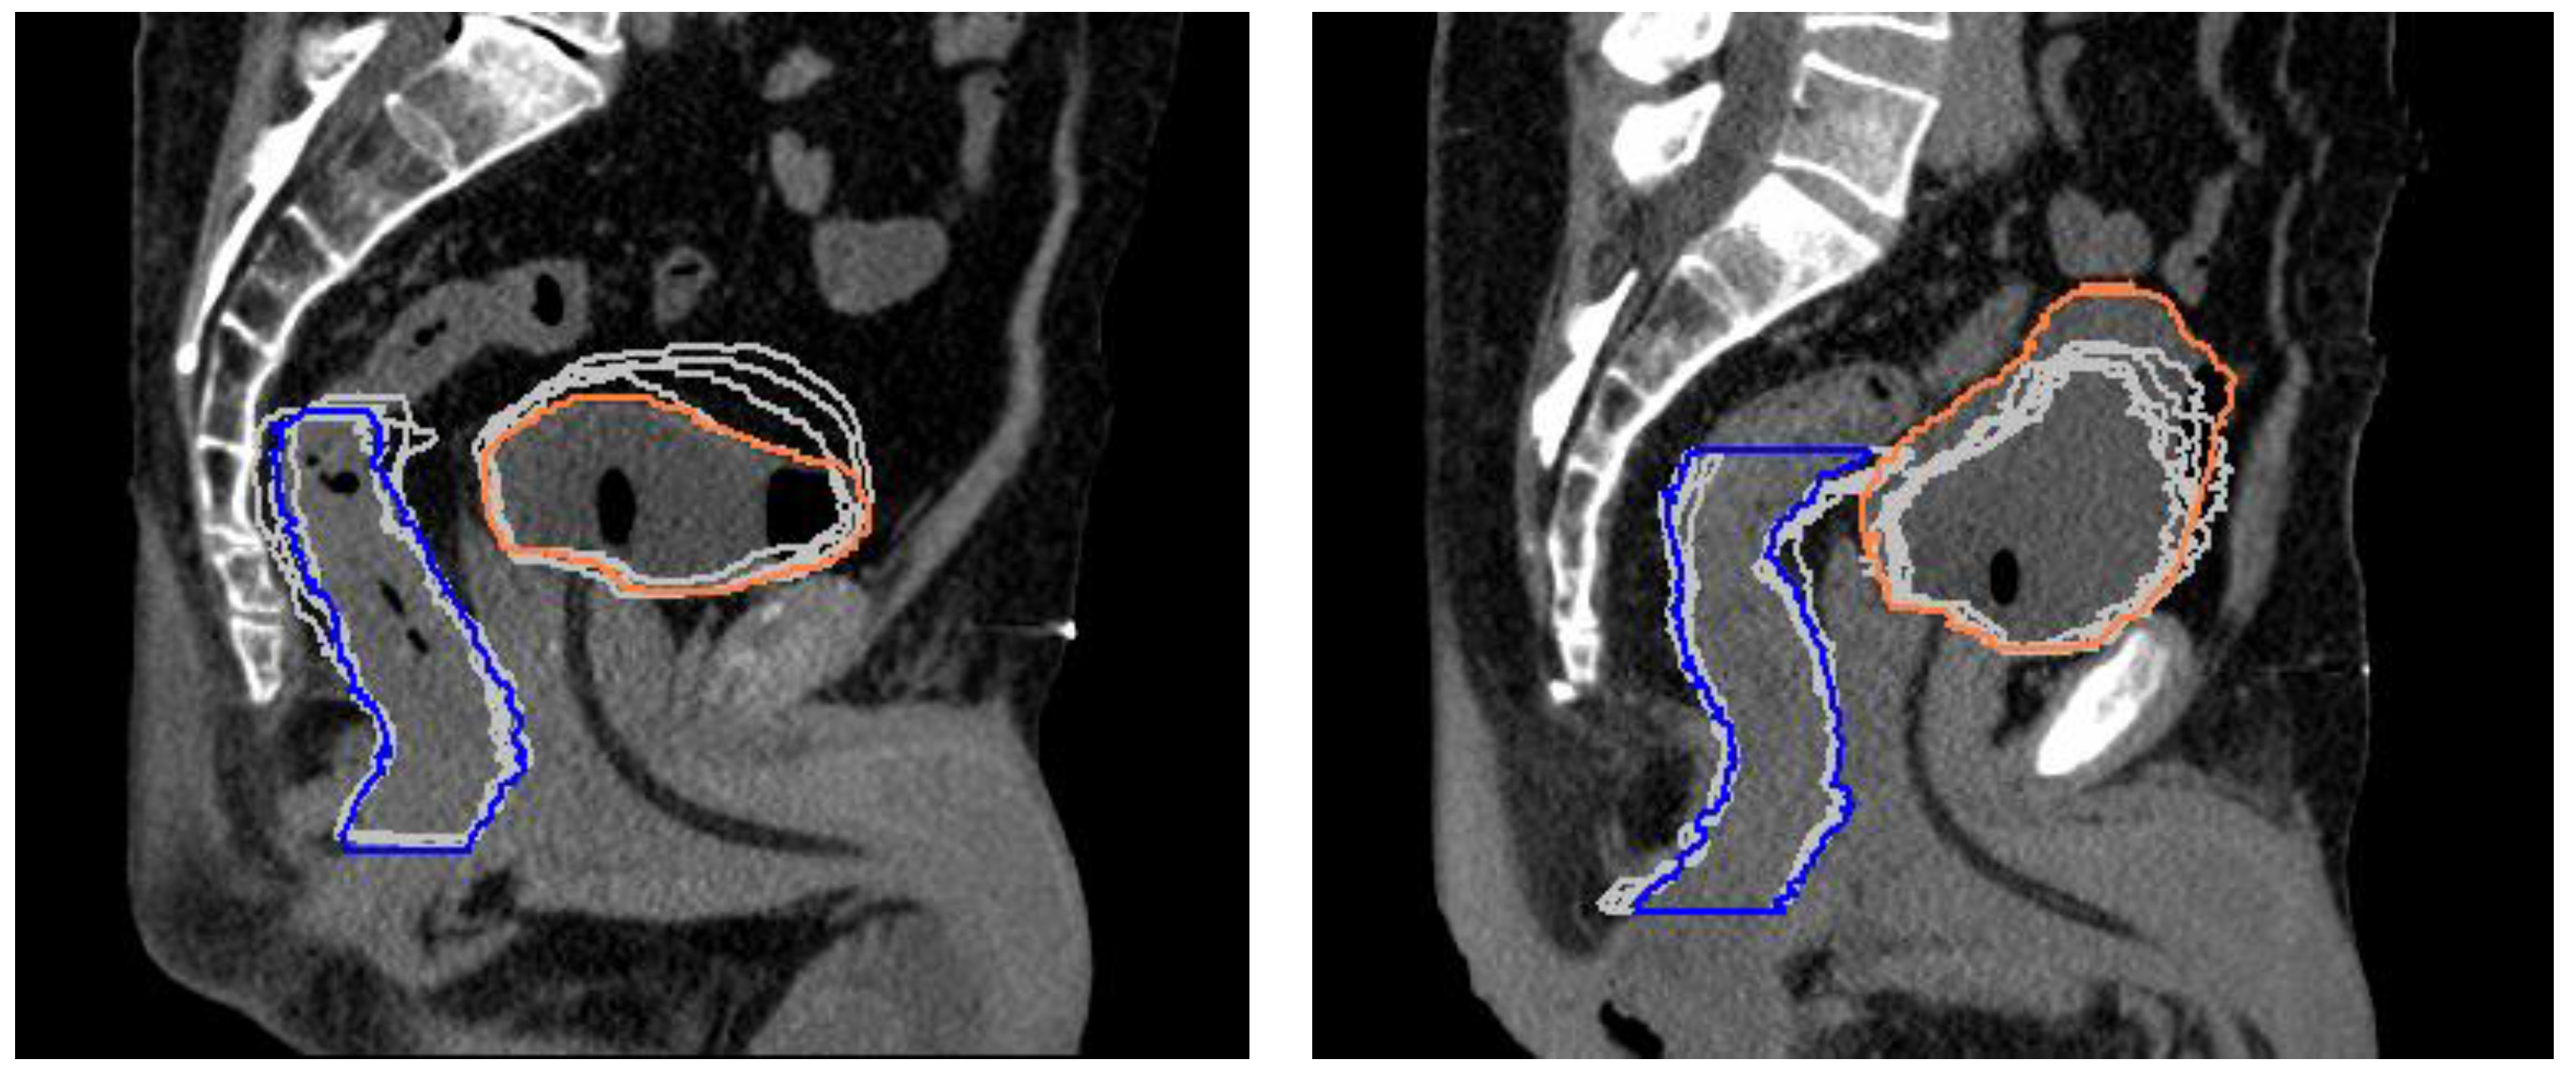

3.2. CTV, Rectum, and Bladder Volume Changes

3.3. Dosimetric Analysis